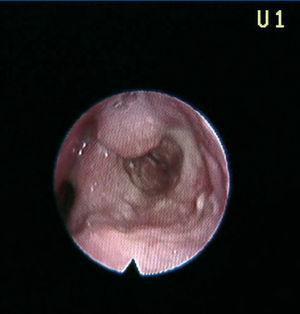

A 41-year-old male, diagnosed with hepatorenal polycystosis received a deceased-donor kidney transplant with immunosuppression with cyclosporin and steroids. He suffered a grade IIb acute interstitial rejection, treated with three boli of 500mg of 6-methylprednisolone. Three and 9 years after the transplant he presented with two episodes of dysphonia; on both occasions with whitish lesions on the arytenoid cartilages and the epiglottis. Anatomopathological diagnosis was tuberculoid granulomatous chronic laryngitis (Figure 2). The Ziehl-Neelsen staining and Löwenstein test were positive. The patient received treatment with isoniazid, rifampicin and pyrazinamide for 2 months and isoniazid and rifampicin for 9 months.

Figure 2. Tuberculous laryngitis